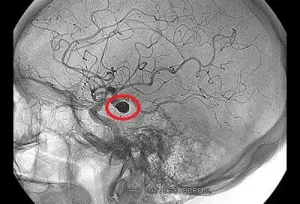

شایعترین نوع سکته مغزی است و حدود ۸۰ درصد موارد را شامل میشود. در این نوع سکته، جریان خون به بخشی از مغز مسدود میشود و به دنبال آن، اکسیژنرسانی به سلولهای مغزی مختل شده و بافت مغز دچار آسیب میگردد. ایسکمیک خود به دو دسته تقسیم میشود:

- سکته ترومبوتیک: علت آن ایجاد لخته خون در یکی از شریانهای مغزی است که به دنبال تصلب شرایین ایجاد میشود. این لخته باعث انسداد رگ و قطع جریان خون به مغز میگردد.

- سکته آمبولیک: لخته یا پلاک کوچکی که در شریانهای خارج از مغز تشکیل شده است، وارد جریان خون شده و در یکی از رگهای باریک مغز گیر میافتد و باعث انسداد جریان خون و در نتیجه سکته میشود.